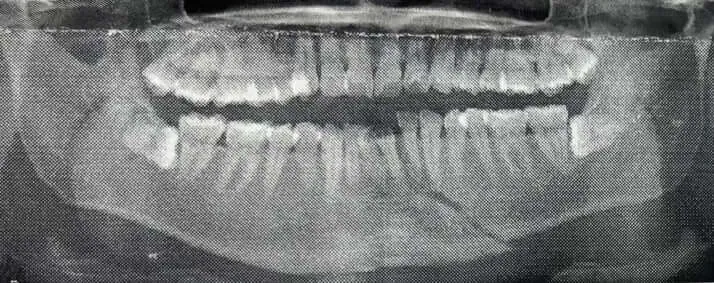

The alleged victim has shown the media pictures he has taken of himself, showing a grotesquely swollen face, almost unrecognizable compared to his former appearance.

The alleged victim recalls: "Kaneko's attacks escalated rapidly. When I tried to block his attacks with my arms, he yelled at me, 'Move your arm, you're in the way! I'll kill you!' Normally, crescent kicks are dangerous and you stop just before they hit you, but he was merciless, hitting me in the head and stomach. He didn't like the towel I was wrapping around my swollen ear to protect it, so he ordered me to 'take it off,' and as a result of continuing to take punches and kicks with all his might, my ear was crushed. My consciousness became hazy and there were more than one times when I thought I might die."